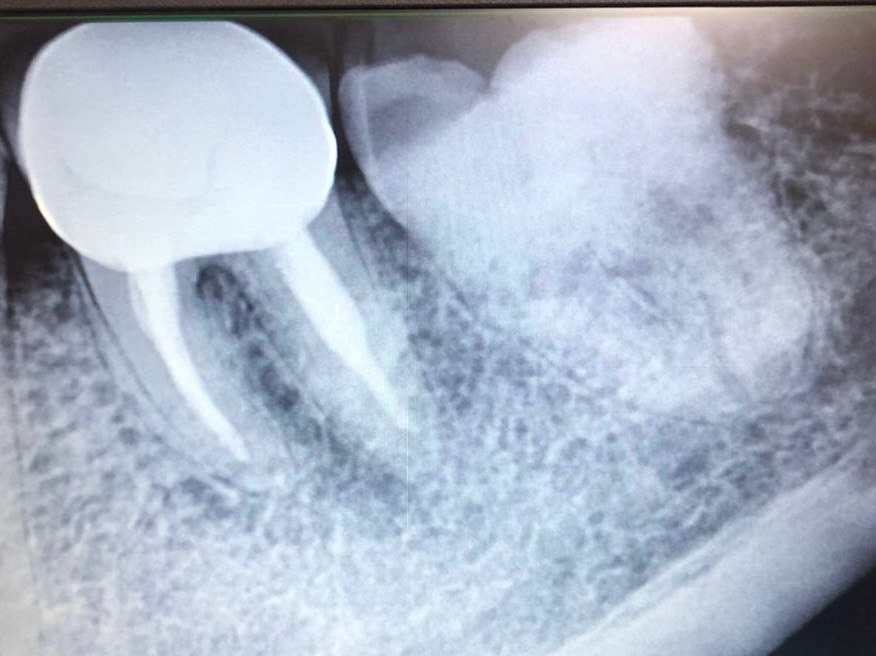

5. What option can be selected for root canal treatment of tooth # 1.5?

6. What option can be selected for root canal treatment of tooth # 1.4?